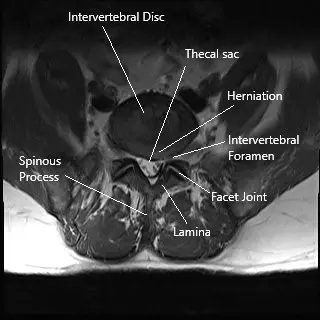

The lumbar spine consists of five vertebrae (L1-L5) with intervertebral discs between them that act as shock absorbers. The spinal cord runs through the spinal canal, and nerves branch out from the cord through small openings called foramina. These nerves transmit signals to various parts of the body, including the legs and feet. When a disc herniates, it can compress these nerves, leading to pain and dysfunction in the lower extremities.

- MRI: The gold standard imaging technique to visualize disc herniation, nerve compression, and other spinal issues.